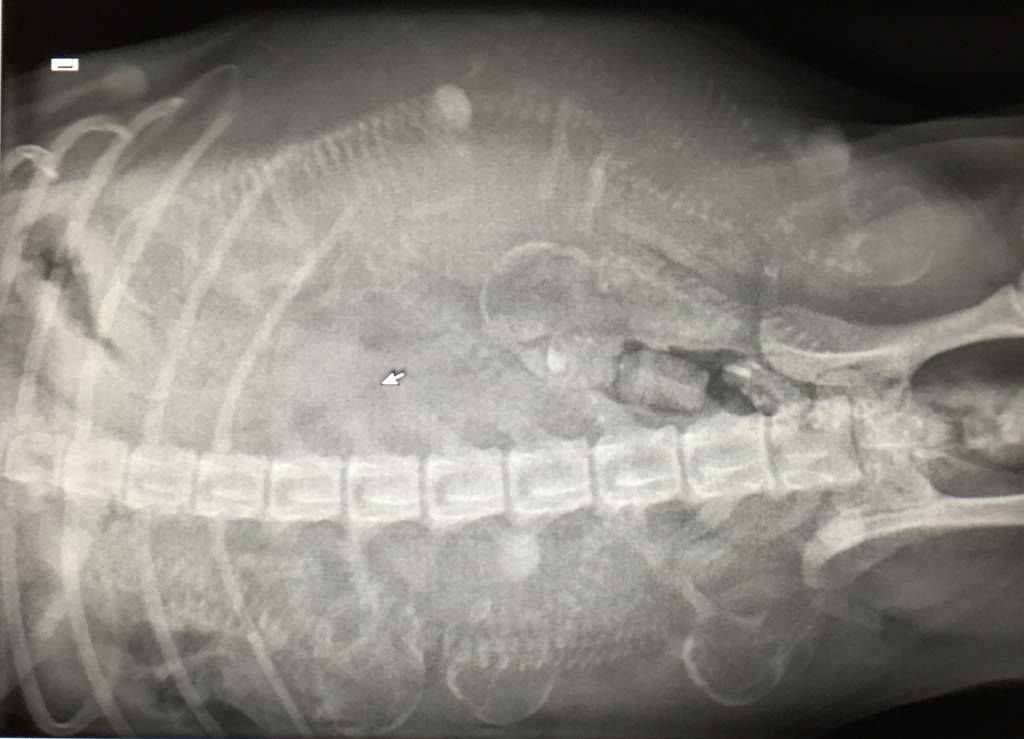

Um nun auch ein wenig Licht in das Dunkel zu bringen und auch gleichzeitig zu sehen, auf was wir uns einstellen müssen, waren wir heute zum Röntgen. Somit können wir heute festhalten, dass wir mindestens 6 Welpen erwarten und eine mögliche Dunkelziffer nicht ausschließen können ......